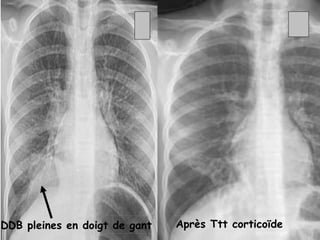

 RX thorax ( face + profil) :

   IMAGES LABILES :

- infiltrat parenchymateux hétérogène, ou péri hilaire

pouvant simuler des ADP.

- opacité systématisée rétractile lobaire ou

segmentaire, uni ou bilatérale, par bouchon muqueux.

- impaction mucoîde : bronchectasies pleines avec

aspect en doigt de gant

DDB pleines en doigt de gant   Après Ttt corticoïde